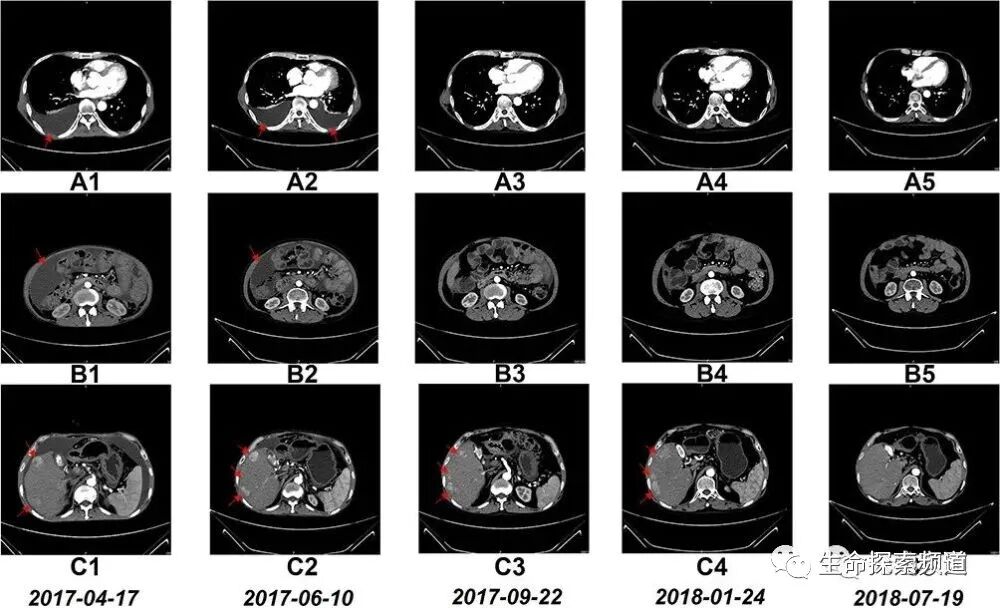

⑤:患者胸腹水達到完全消失,肝右葉的多個腫瘤也不同程度的縮小。值得一提的是在治療6個療程時,患者胸腹水就出現(xiàn)明顯減少的好轉(zhuǎn),在17個療程結(jié)束后進行了CT檢查,驚喜的發(fā)現(xiàn)肝右葉的瘤體也明顯縮小。

CT掃描A1-5:6個療程后胸腔積液清除。

CT掃描B1-5:6個療程后腹水幾近清除。

CT掃描C1-5:17個療程后肝右葉的瘤體明顯縮小。